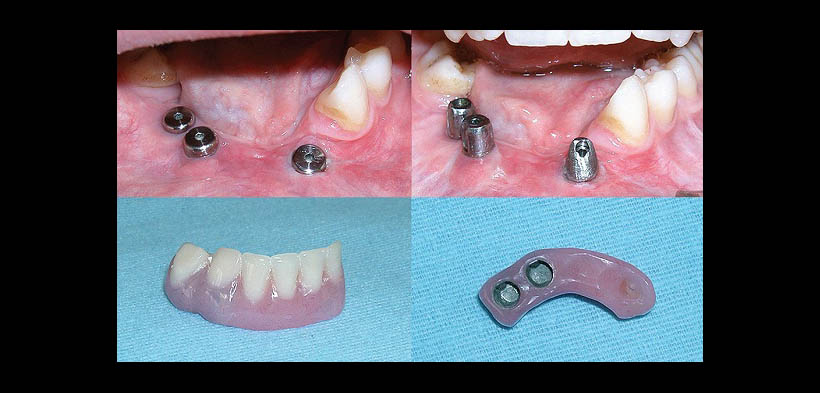

Fig. 6. Colocación de implantes dentales a 6 años del diagnóstico inicial de GCCG, confección de la prótesis parcial implantosoportada.

Fig. 7. Fotografía final del tratamiento multidisciplinario resultado del seguimiento de 6 años del diagnóstico inicial de GCCG.